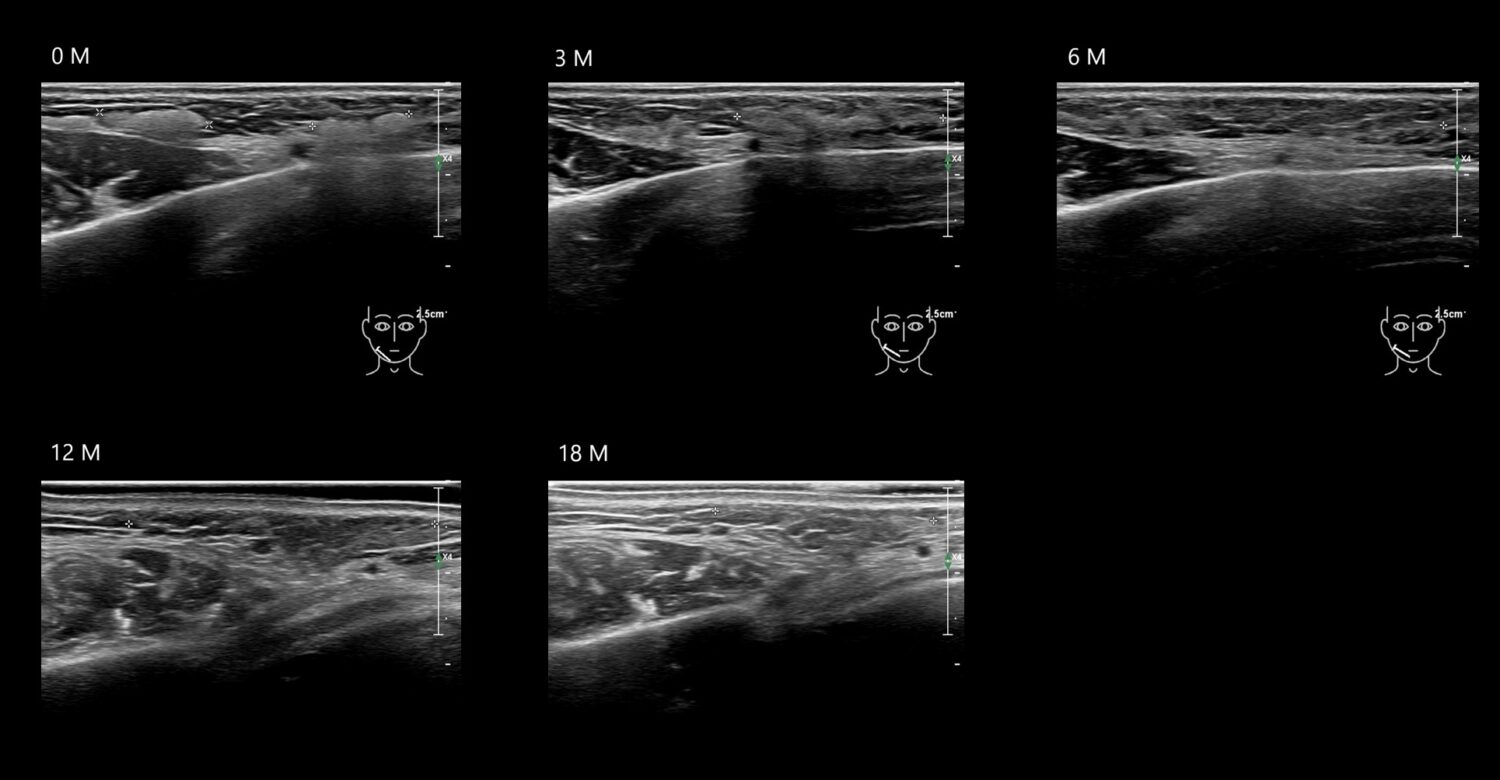

Filler library